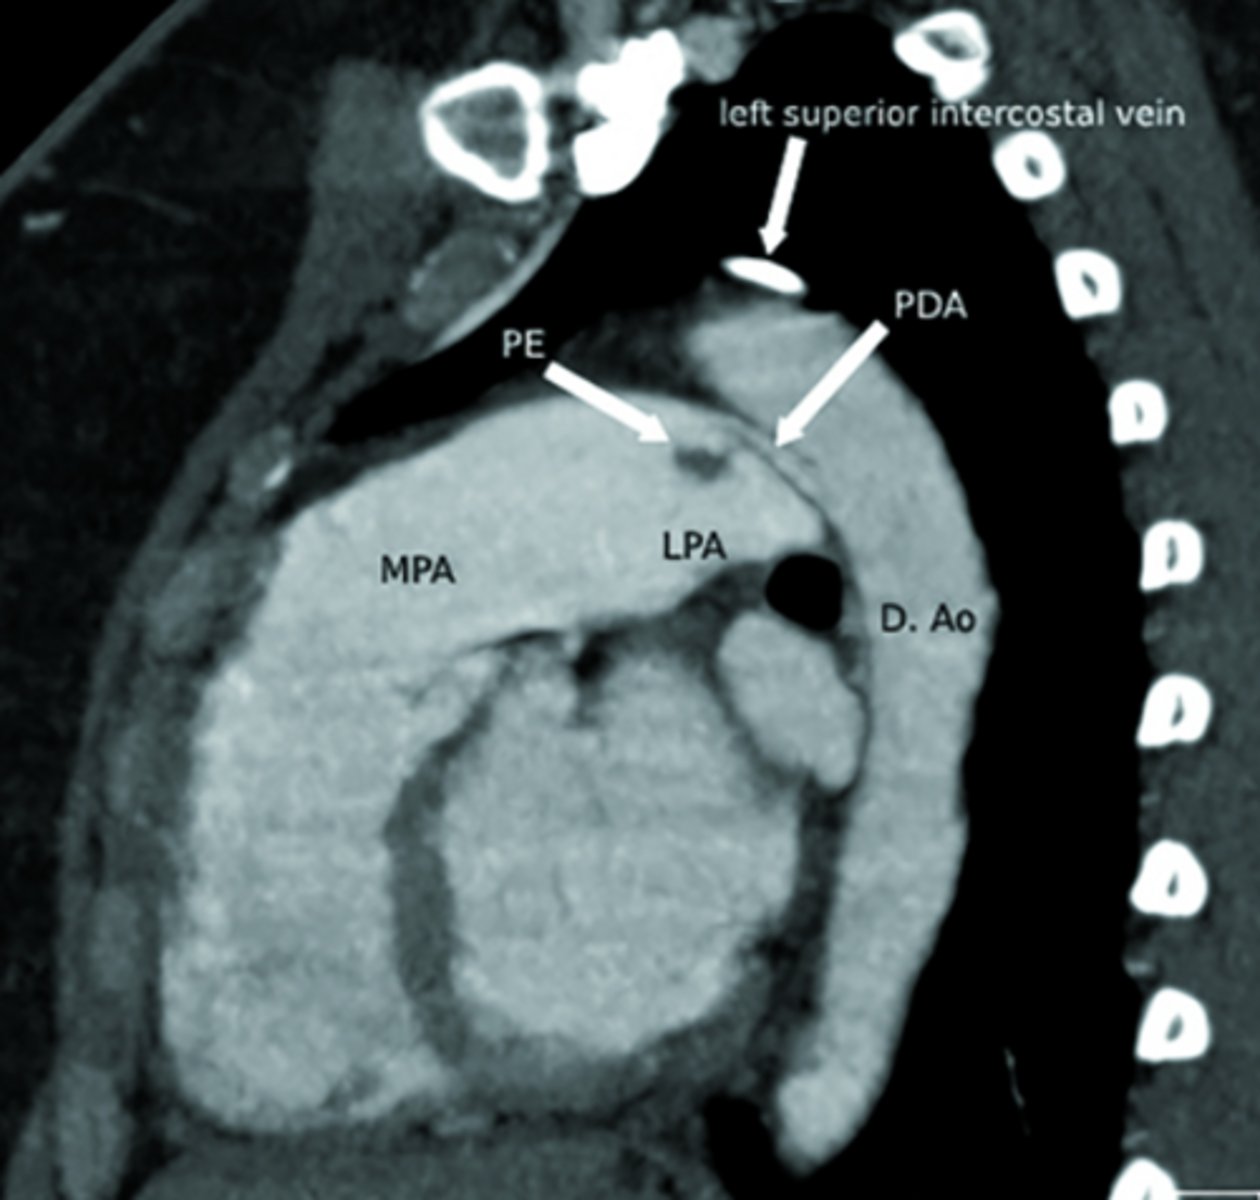

What is patent ductus arteriosus (PDA)?

Persistent connection between the pulmonary artery and aorta after birth.

<p>Persistent connection between the pulmonary artery and aorta after birth.</p>

Left proximal portion of Arch 6 forms what?

Left pulmonary artery (think LP LP)

Left distal portion of Arch 6 persists as what?

Ductus arteriosus